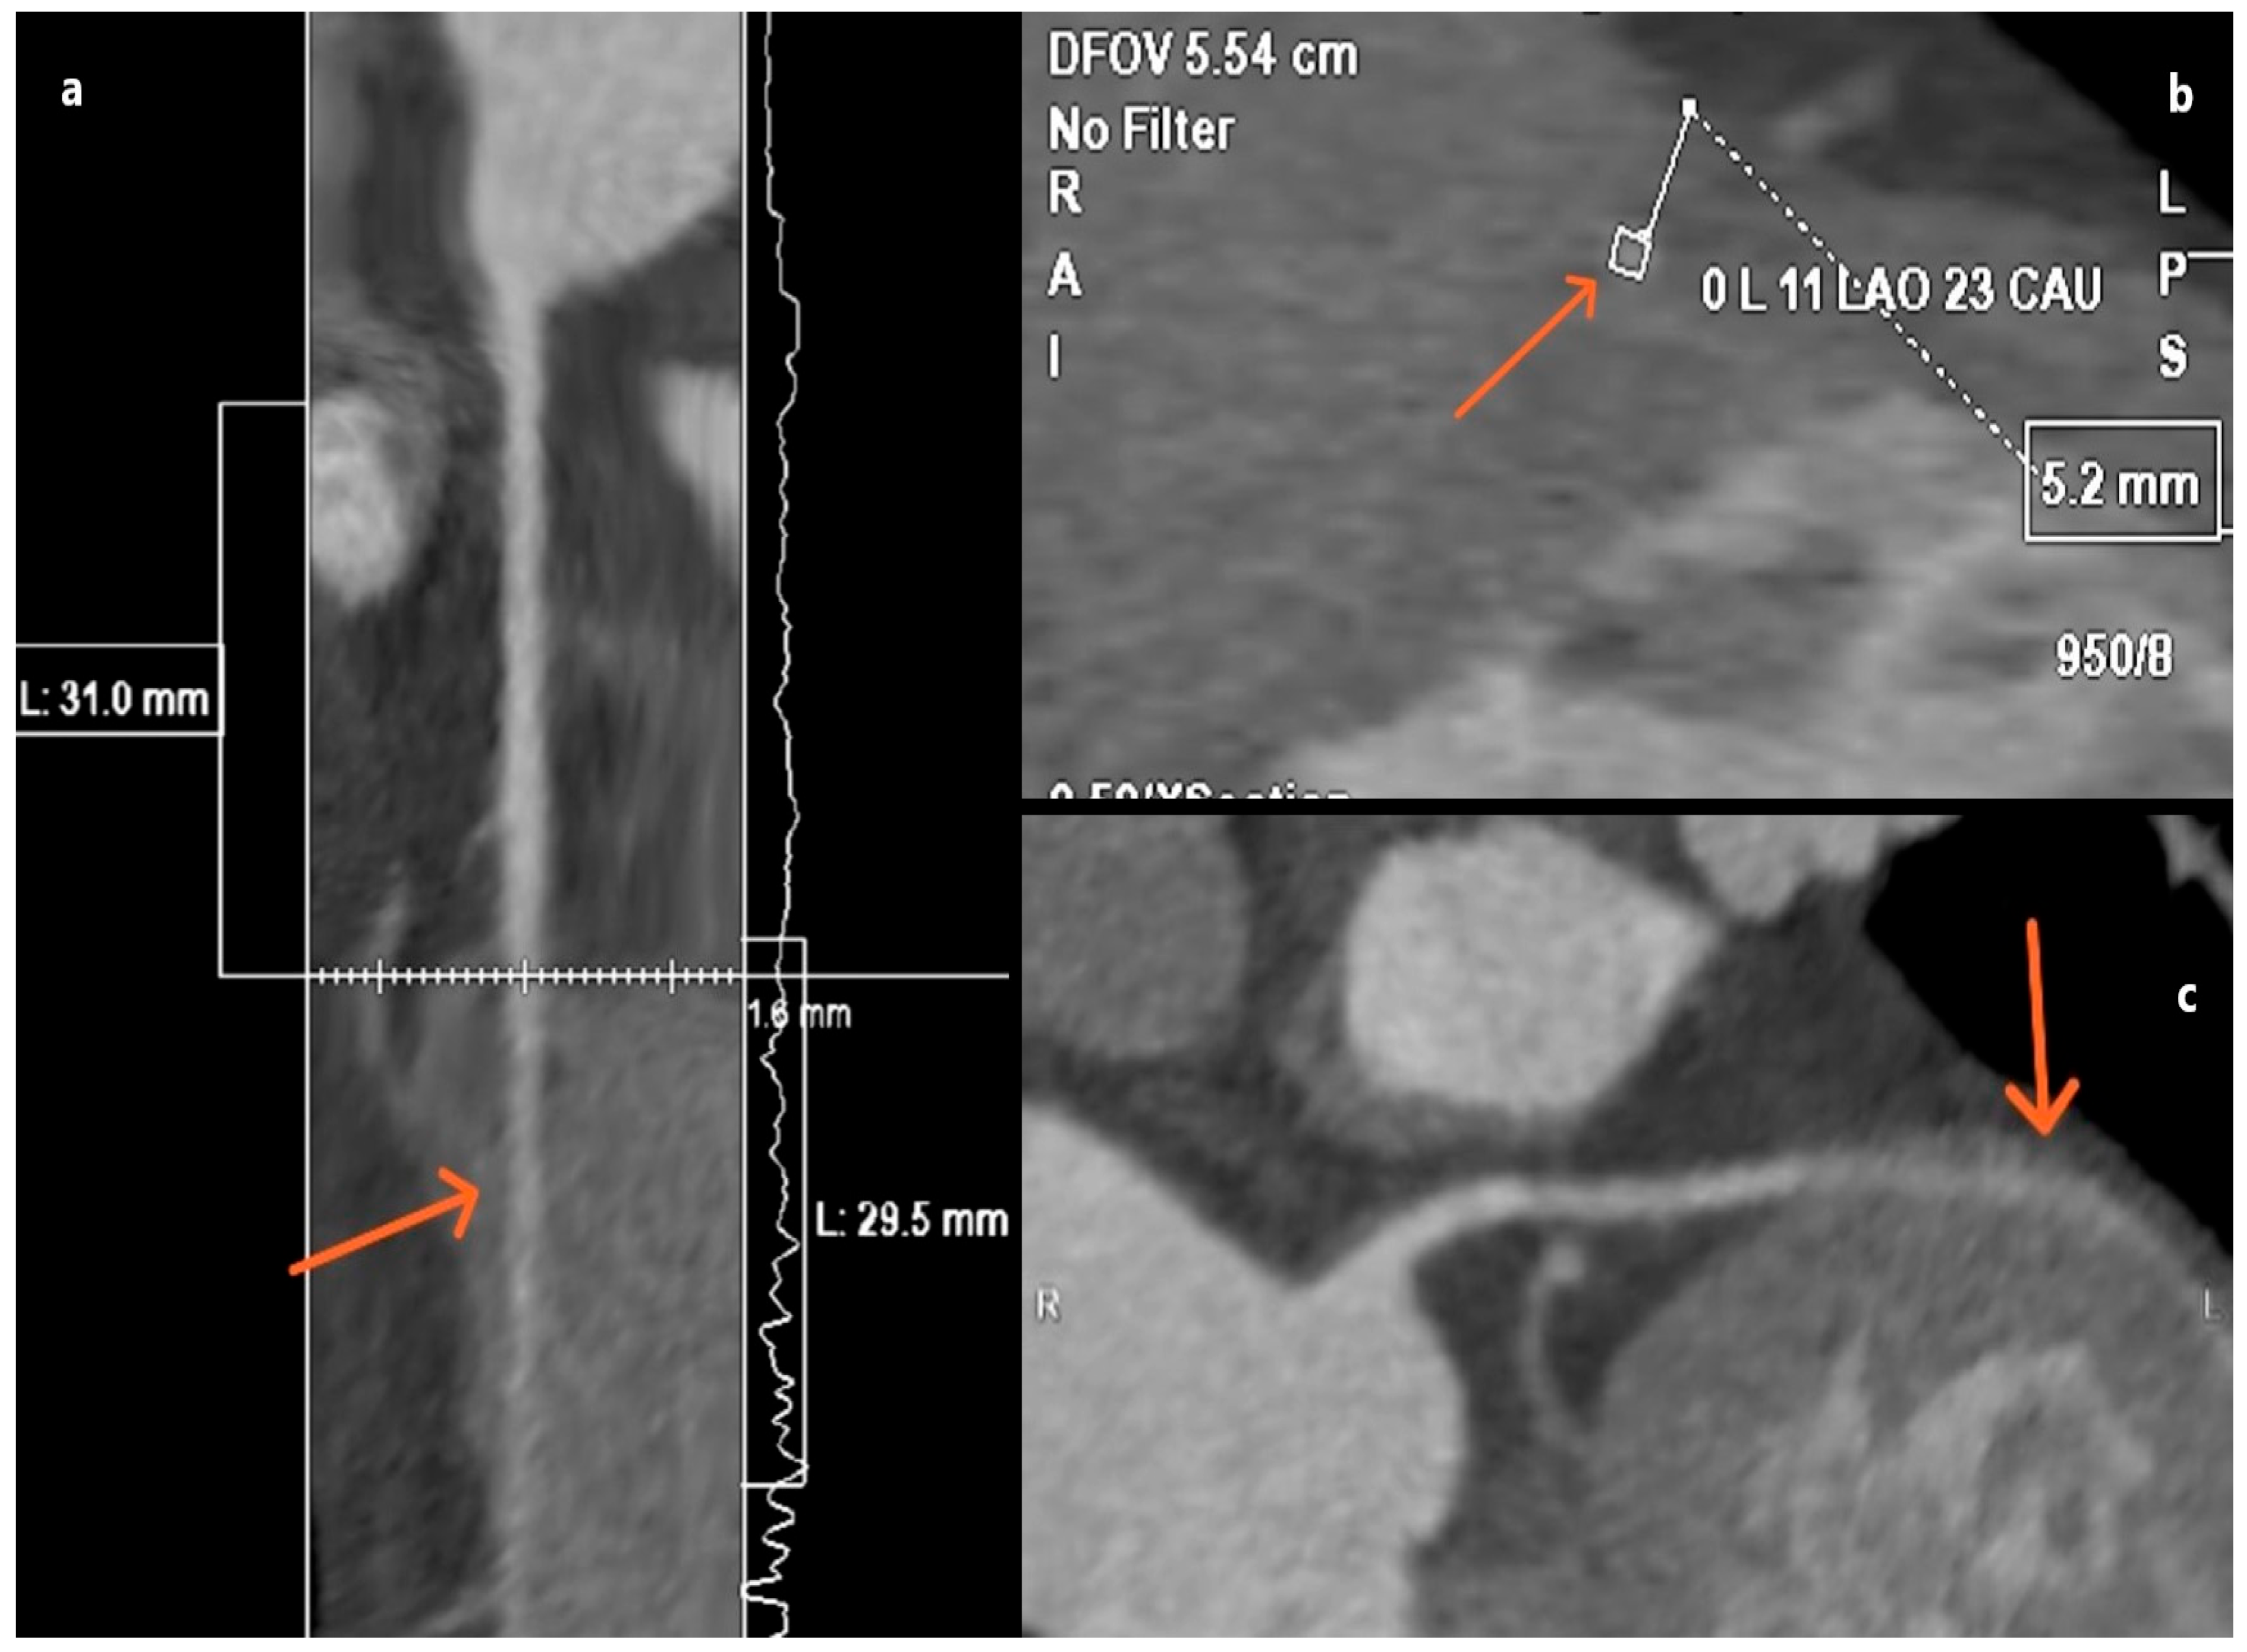

3.1. Myocardial Bridge